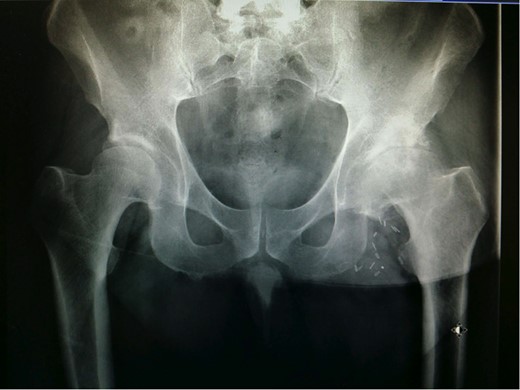

X-ray (Fig. 1) showed severe loss of joint space, subchondral cyst formation and sclerosis, confirming the clinical findings of advanced left hip osteoarthritis. Additionally, concomitant femoral head flattening was detected on X-ray, consistent with possible osteonecrosis.